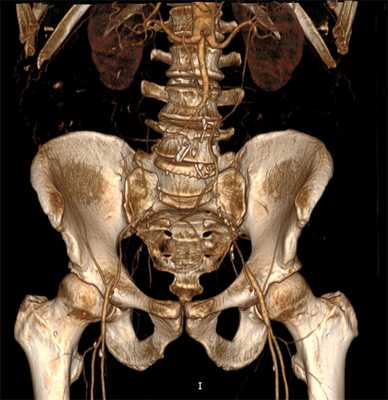

Мультиспиральная компьютерная томография проводится при наличии времени для детальной диагностики и позволяет очень точно выявить характер поражений и определить лечебную тактику.

Мультиспиральная компьютерная томография с контрастом

С целью подготовки к хирургическому лечению необходимо детально выяснить состояние артерий ноги, для этого недостаточно только УЗИ диагностики. Применяется мультиспиральная компьютерная томография с контрастом. Это исследование позволяет получить изображение сосудистого русла в трёхмерном формате и правильно спланировать хирургическое вмешательство, определиться с его видом. В нашей клинике МСКТ выполняется перед каждой реконструктивной сосудистой операцией или ангиопластикой.